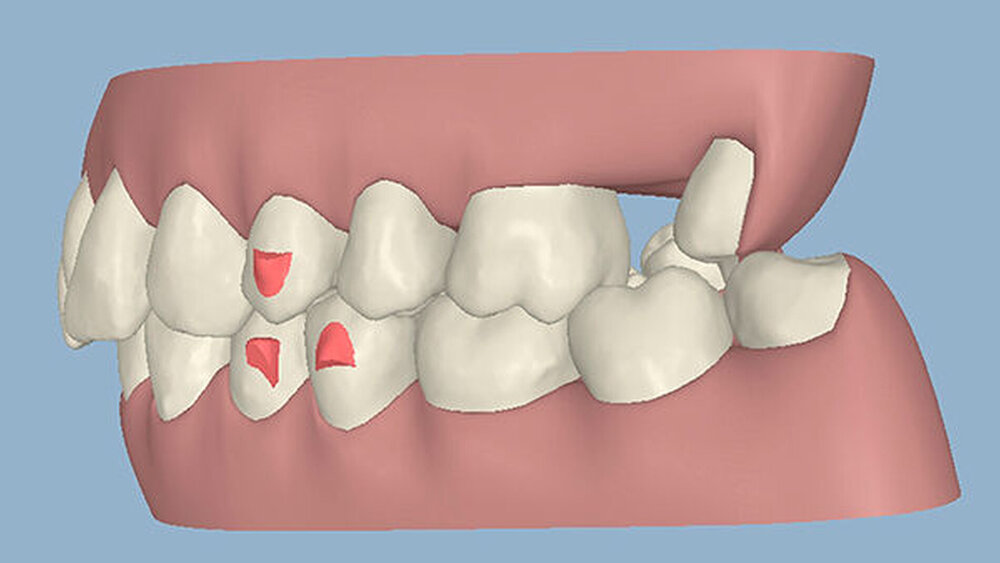

Kieferorthopädisch imponierte beidseits eine neutrale Verzahnung bei einem tiefen Biss von 5 mm - bedingt durch die Verlängerung beider Frontzahngruppen. Besonders Zahn 11 zeigte eine erhebliche Verlängerung und Protrusion mit einer sagittalen Frontzahnstufe von 5 mm. Sowohl die Frontzähne im Ober- als auch im Unterkiefer wiesen eine lückige Beziehung zueinander auf (Abbildung 1).

Die Sulkustiefen konnten auf etwas weniger als 4 mm reduziert werden, während der Blutungs- und Plaque-Index bei weniger als 15 Prozent lag. Daher wurde eine kieferorthopädische Behandlung über die nächsten zwei Jahre in Kombination mit engen zahnärztlichen Kontrollen geplant. Als Mittel der Wahl entschieden wir uns gemeinsam mit dem Patienten für das Invisalign-System, da hiermit sowohl eine Schienung als auch eine kraft-arme Bewegung der Zähne möglich sein sollte. Für den Frontzahnbereich wurden keine Attachments geplant, so dass hier eine unnötige Hebelwirkung umgangen werden konnte (Abbildung 3).